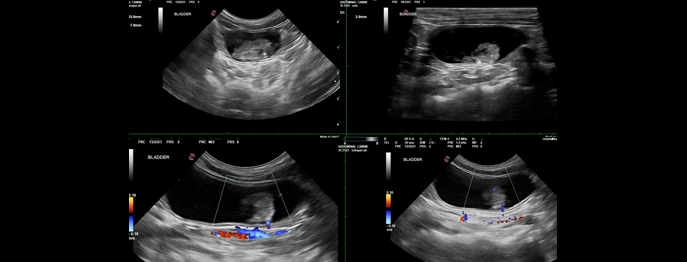

Sonographie der Harnblase bei Hund und Katze

Typische und atypische Veränderungen

In diesem vetinar widmen wir uns den sonographischen Veränderungen der Harnblase bei Hund und Katze.

Besprochen werden typische und atypische Befunde wie Wandverdickungen, intraluminale Strukturen, Harnblasensteine, Neoplasien und entzündliche Veränderungen. Anhand praxisrelevanter Beispiele werden sonographische Merkmale, Differenzialdiagnosen sowie Fallstricke der Interpretation erläutert.